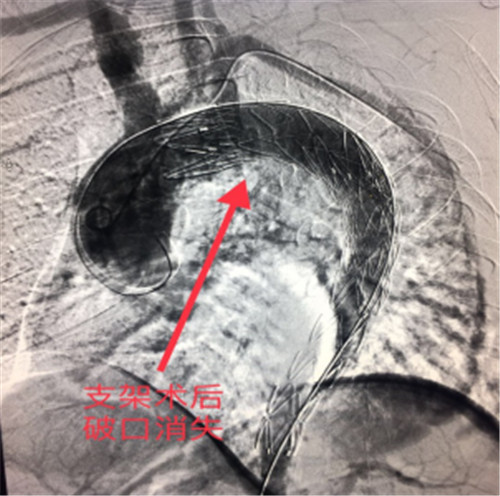

术中多学科团队密切协作,严密监测、控制患者心率、血压,手术取得圆满成功,术后患者各项生命体征平稳,双侧桡动脉、股动脉搏动良好,患者无头晕等脑缺血症状,目前正在进一步康复中。

胸主动脉夹层起病急、发展快、死亡率极高,若不及时有效治疗,48小时内死亡率70%左右,一周内的死亡率高达90%左右。该患者胸主动脉夹层破口距离左锁骨下动脉开口不足1厘米,为患者实施覆膜支架成功修复腔内破口、部分保留左锁骨下动脉避免了术后出现左上肢无脉症、脑缺血等严重并发症,该术式是目前主动脉夹层介入治疗的首选,较传统外科开胸手术创伤大、高风险、术后恢复慢,介入覆膜支架植入术具有微创、高效、安全等优势。